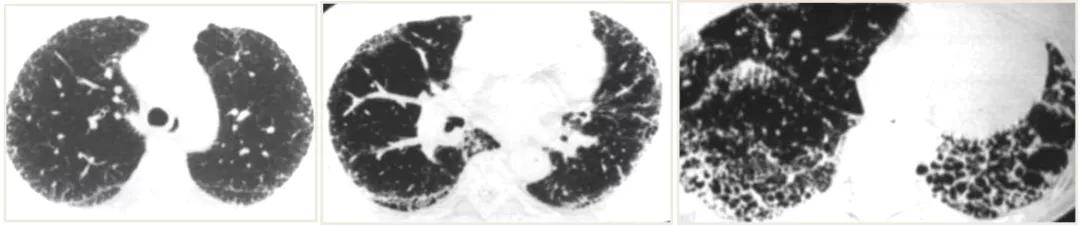

间质性肺疾病 (ILD)/ 弥漫性实质性肺疾病(DPLD)是指由许多已知或未知原因引起的一组弥漫性肺疾病的总称。它们具有共同的病理特征,如累及部位为肺泡壁和肺泡腔, 病变特征 主要是「炎症和纤维化」,但是这些病变形式、程度和分布不同(下图),形成不同类型的间质性肺炎和不同的临床表型;共同的 临床、病理生理特征 是呼吸困难,肺功能呈换气功能障碍和限制通气功能障碍,影像显示为胸部广泛浸润影。

图:不同类型间质性肺炎的病理表现

从 病理 来看,有肺泡、小叶间隔间隔增厚,还有成纤维细胞增生,胶原沉积,最后导致蜂窝肺,肺结构破坏。

从 影像学 看,高分辨CT显示有磨玻璃样改变、网格,蜂窝,还有牵拉性的支气管扩张,最后导致肺结构破坏。

图:纤维化性间质性肺疾病的影像与病理改变 [9-12]